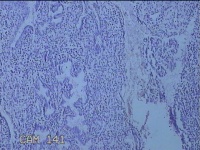

宫腔内容物

性别

女

年龄

47岁

临床诊断

1.异常子宫出血 2.慢性宫颈炎

一般病史

不规则阴道流血21天。

标本名称

大体所见

灰白暗红色不规则碎组织2.5x1.8x0.3cm一堆。

图3